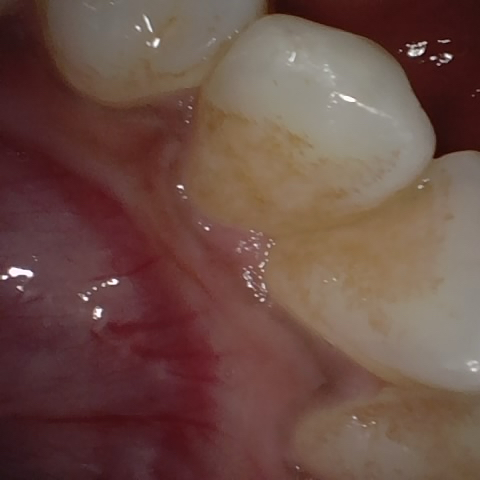

NHD9283

Annotated as "Good"